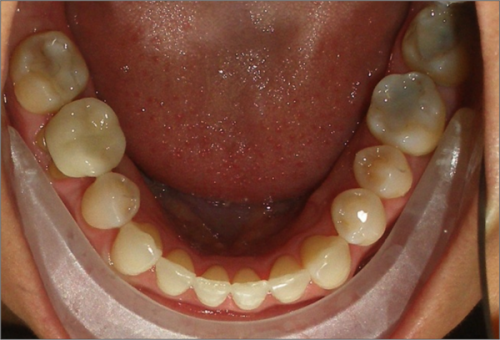

45 year old female:

Diagnosis:

- Missing upper left second bicuspid

- Lower arch crowding

- Edge to edge bite

Treatment:

- Extraction of upper & lower right second bicuspids

- Full fixed appliances

- 21 months